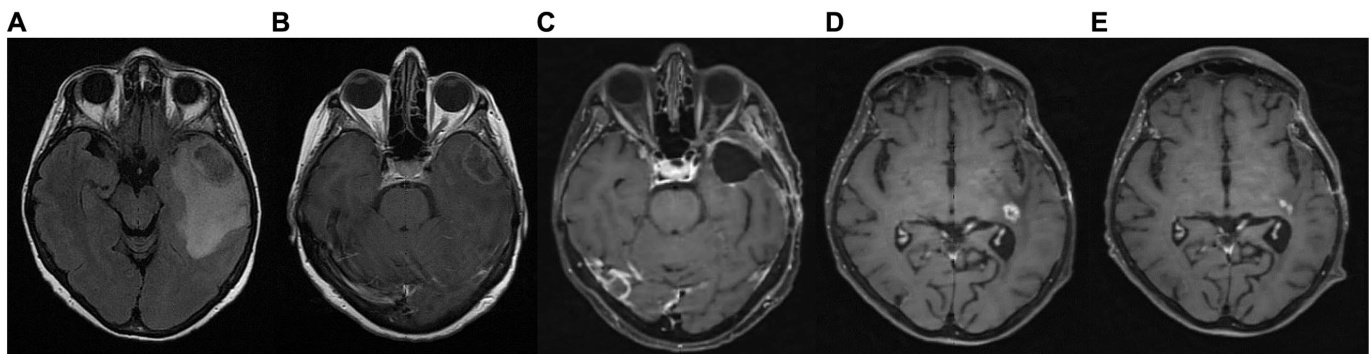

A 65-year-old female was diagnosed with GBM in April 2021. Her presenting symptom was anomic aphasia. Brain MRI was remarkable for a space-occupying lesion at the left temporal lobe with he t erogenous signal on T2 sequences and irregular enhancement surrounded by large vasogenic oedema, consistent with GBM (Figure 6). Her his to pathological examination confirmed IDH1-negative GBM (Figure 4). She underwent surgery (total resection of the tumor) followed by radiotherapy—a total of 60 Gy in 30 RTs - and maintenance chemotherapy with temozolomide $120\mathrm{mg/m^{2}/d a y,}$ for 5 days each month. Ketogenic diet with a ketogenic ratio of $>2:1$ and total daily calorie intake of 1,500 kcal/day was introduced in July of the same year (Table 3). After 6 months the patient decided to abandon the diet due to perceived dietary restrictive ness. On April 2022, 4 months after KD discontinuation, GBM recurrence was followed by stereo tactic radio surgery (CyberKnife) (Figure 6). She also initiated second line chemotherapy with bevacizumab $(5{-}7\mathrm{mg/kg)}$ and irinotecan $120\mathrm{mg/}$ $\mathrm{m}^{2}$ twice/month, which is maintained until the present day. After relapse, the patient agreed to reinitiate the diet with improved adherence. Blood glucose levels were maintained between 75 and $85\mathrm{mg/dL}$ and ketone levels between 2 and 3 mmol/L. Her present ECOG grade is 0.

一名65岁女性于2021年4月被诊断为胶质母细胞瘤(GBM),首发症状为命名性失语。脑部MRI显示左颞叶占位性病变,T2序列呈不均匀信号伴不规则强化及周围大面积血管源性水肿,符合GBM表现(图6)。组织病理学检查确诊为IDH1阴性GBM(图4)。患者接受肿瘤全切手术后,进行了30次总剂量60Gy的放疗,并采用替莫唑胺维持化疗(120mg/m²/天,每月连用5天)。同年7月开始生酮饮食(生酮比>2:1,每日总热量摄入1500kcal)(表3)。6个月后患者因感觉饮食限制过多而中止该方案。2022年4月(停用生酮饮食4个月后)肿瘤复发,遂接受立体定向放射外科治疗(CyberKnife)(图6),并开始二线化疗方案:贝伐珠单抗(5-7mg/kg)联合伊立替康(120mg/m²,每月两次),该方案持续至今。复发后患者同意重新开始生酮饮食且依从性提高,血糖维持在75-85mg/dL,血酮水平维持在2-3mmol/L。目前ECOG评分为0分。

FIGURE 6 Patient 3: (A) brain MRI on diagnosis (T2/FLAIR) (B) brain MRI on diagnosis (T1 with contrast) (C) 9-month follow up brain MRI (T1 with contrast) (D) GBM relapse, 12-month follow up brain MRI (T1 with contrast) (E) 30-month follow up brain MRI (T1 with contrast).

图 6 患者3: (A) 确诊时脑部MRI (T2/FLAIR) (B) 确诊时脑部MRI (增强T1) (C) 9个月随访脑部MRI (增强T1) (D) GBM复发, 12个月随访脑部MRI (增强T1) (E) 30个月随访脑部MRI (增强T1)。